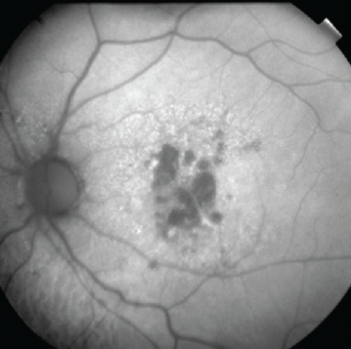

D’autres domaines de progrès sont le diagnostic et le suivi. L’autofluorescence du fond d’œil (AF) est une technique d’imagerie utile pour obtenir une définition plus claire des zones de cellules endommagées dans les cas de DMLA sèche. Les images peuvent être associées à des algorithmes d’IA pour aider à suivre l’évolution de la maladie et surveiller la croissance des lésions. Lorsque cette technologie d’apprentissage automatique sera largement accessible à l’échelle clinique, elle nous fournira un autre outil pour surveiller les formes avancées de DMLA.